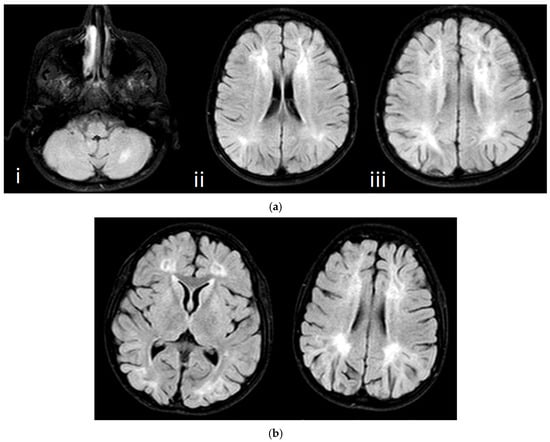

| MRI | Brain: Normal Spine: Normal | Brain: Normal Spine: Normal | Brain: Abnormal Spine: Normal | Brain: Abnormal Spine: Normal (Figure 4a) | Brain: Abnormal Spine: Normal (Figure 4b) |